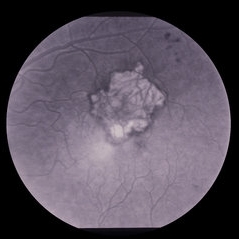

Fluorescein angiogram ARMD. ARMD Laser Rx

Condition/keywords: neovascular age-related macular degeneration (AMD)